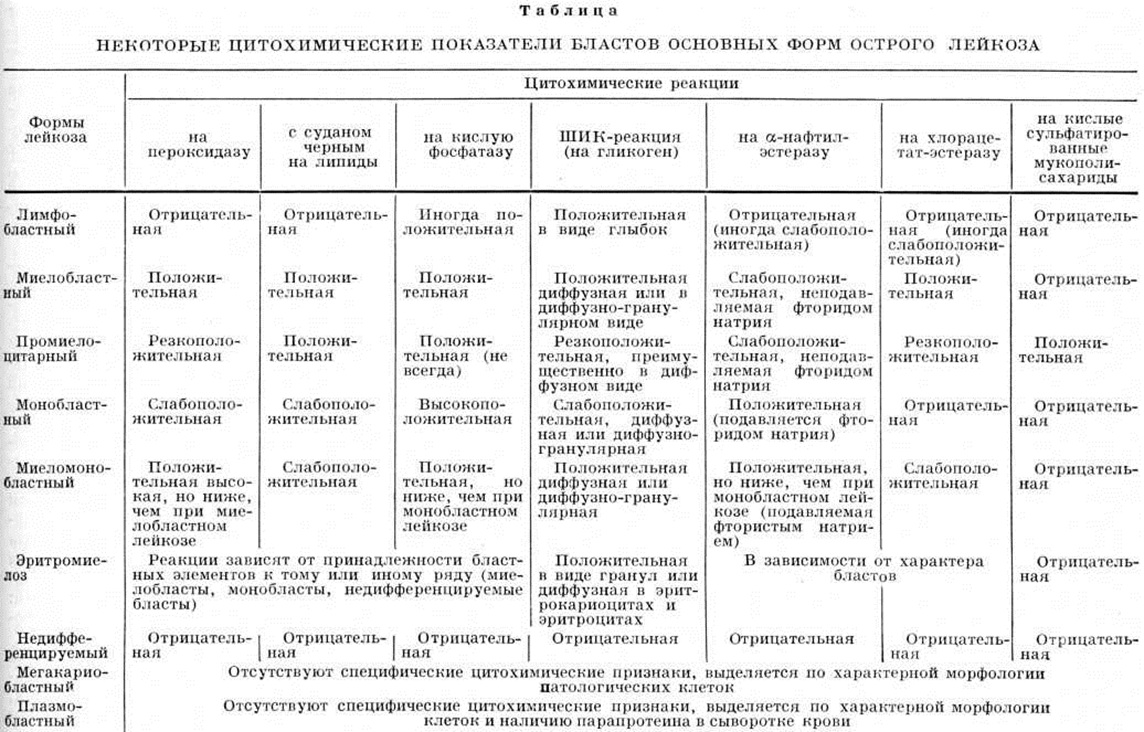

При микроскопическом исследовании дифференциальная диагностика форм острого Лейкозы основывается на цитохимические особенностях бластных клеток, образующих лейкозные разрастания. Строение бластных клеток, частота специфического поражения различных внутренних органов, характер расположения в них лейкозных инфильтратов отличаются при разных формах весьма относительно, в связи с чем не могут служить основными критериями для установления формы острого Лейкозы

В практической работе патологоанатомов при исследовании материала биопсий, полученного из кроветворных органов, и секционного материала форма острого Лейкозы обычно устанавливается с учётом данных цитохимические изучения прижизненных мазков периферической крови и пунктатов костного мозга. Идентификация формы острого Лейкозы при исследовании тканевых срезов осуществляется с помощью гистохимические методик, включающих методы определения пероксидазы, гликогена на основании ШИК-реакции (смотри полный свод знаний), активности неспецифической эстеразы (с субстратом α-нафтилацетата и инкубацией контрольных срезов в среде с добавлением фторида натрия). Для контроля и более детальной дифференциации обычно проводят также выявление липидов Суданом черным Б, активности хлорацетатэстеразы, кислой фосфатазы. Гистохимические исследованию подлежат ткани, взятые только в первые часы после смерти. Оценку результатов следует проводить на тонких срезах (до 5 микрометров) при большом увеличении микроскопа. В связи с тем, что в тканевых срезах трудно выявить положительную ШИК-реакцию в гранулярной форме и степень активности кислой фосфатазы, особенно при небольшом количестве положительно реагирующих бластов, гистологический исследование целесообразно сочетать с цитохимические изучением клеток в отпечатках с кроветворных органов. У леченых больных определение формы острого Лейкозы затруднено в связи с частым изменением цитохимические свойств бластов под влиянием цитостатических средств. В таких случаях при исследовании биопсийного и секционного материала форма острого Лейкозы диагностируется на основании результатов цитохимические изучения лейкозных клеток периферической крови и костного мозга до начала лечения. Некоторые цитохимические показатели бластов основных форм острого лейкоза представлены в таблице.

Ядра бластных клеток имеют нежно-структурную хроматиновую сеть, нередко несколько мелких нуклеол. Цитоплазма бластных клеток содержит ауэрофильную зернистость или тельца Ауэра, даёт положительную реакцию на миелопероксидазу, липиды, хлорацетатэстеразу, диффузно окрашивается при ШИК-реакции. Активность неспецифической эстеразы низкая. С миелопероксидазой связано появление зеленоватой окраски на разрезе лейкемических инфильтратов — хлором. С течением болезни бластные клетки могут приобрести новые черты: расширение и деформация цитоплазмы, исчезновение зернистости, что обычно сопровождает появление новых опухолевых клонов.

При миеломонобластной форме острого лейкоза в бластах цитохимически выявляется не только пероксидаза, но и α-нафтилэстераза, характерная для элементов моноцитарного ряда, она подавляется фторидом натрия.

Острый лимфобластный лейкоз, как правило, с самого начала протекает с лимфаденопатией, увеличением лимфатических, узлов, селезёнки и оссалгиями. В крови вначале может отмечаться лишь умеренная нормохромная анемия, ускорение РОЭ. Бластные клетки с округлым ядром с нежной сетью хроматина и одной-двумя нуклеолами, беззернистой узкой цитоплазмой. Характерной их особенностью является положительная гранулярная ШИК-реакция, отсутствие пероксидазных и суданофильных включений в цитоплазме. Реакция на неспецифическую эстеразу отрицательная или слабоположительная. Высокая активность кислой фосфатазы отмечена при редком Т-клеточном варианте.

Острый промиелоцитарный лейкоз довольно редок и характеризуется быстротой течения. Ему присущи выраженная кровоточивость, гипофибриногенемия. Периферические лимфатические узлы, печень и селезёнка обычно не увеличены. В гемограмме отмечается анемия, выраженная тромбоцитопения; в костном мозге высокий процент атипических бластов. Бластные клетки различны по величине и форме, с голубоватой цитоплазмой, густо заполненной крупной фиолетово-бурой зернистостью, располагающейся и на ядрах, нередки тельца Ауэра. Зернистость содержит кислые сульфатированные мукополисахариды. Ядра этих лейкозных клеток округлые или бобовидные, с нежной или грубоватой структурой хроматина, одной-тремя нуклеолами, занимают меньшую часть клетки. В цитоплазме клеток большое количество лизосом. Эти клетки имеют лишь отдалённое сходство с промиелоцитами и относятся к предшественникам гранулоцитов. Клетки дают положительную реакцию на пероксидазу, липиды, хлорацетатэстеразу, неспецифическую эстеразу, диффузное окрашивание цитоплазмы при ШИК-реакции. Специфическим цитохимическим признаком служит обнаружение в клетках кислых сульфатированных мукополисахаридов.

Острый монобластный лейкоз относительно редок. Типичное начало этой формы мало отличается от миелобластной. Часто отмечается гиперплазия слизистой оболочки дёсен из-за пролифератов в них. В крови обнаруживается высокий процент гранулоцитов с омоложением. Бластные клетки имеют бобовидное ядро с несколькими нуклеолами и серовато-голубоватую цитоплазму, иногда со скудной азурофильной зернистостью. Цитохимически выявляется положительная реакция на α-нафтилэстеразу, подавляемая фторидом натрия; реакция на пероксидазу, липиды, ШИК-реакция выражены слабо или отсутствуют. Активность кислой фосфатазы умеренная или высокая. В сыворотке крови и моче этих больных высок уровень лизоцима. Эта форма острого Лейкозы плохо поддаётся лечению, ремиссия достигается редко.

Острый плазмобластный лейкоз характеризуется появлением в костном мозге и крови плазмобластов и плазмоцитов с чертами клеточного атипизма, а также недифференцированных бластов. Цитохимические методы не выявляют пероксидазы. Нередко выражены экстрамедуллярные лейкозные очаги — лейкемиды кожи, увеличенные лимфатических, узлы, печень, селезёнка. Особенность данной формы острого Лейкоза — наличие в крови парапротеина.

Острый мегакариобластный лейкоз очень редок. Для него характерно присутствие в костном мозге и крови мегакариобластов — клеток с бластным, но гиперхромным ядром, узкой цитоплазмой с нитевидными выростами, а также недифференцированных бластов. Нередко в крови и костном мозге встречаются уродливые мегакариоциты и осколки их ядер. Характерен тромбоцитоз (более 1 000 000 в 1 микролитров). Дифференцировать данную форму с хронический миелолейкозом при бластном кризе позволяет отсутствие Ph-хромосомы.

Острый эритромиелоз (синдром Ди Гульельмо) встречается сравнительно редко. Периферические лимфатических, узлы обычно не увеличены, в редких случаях наблюдается увеличение печени и селезёнки. Источник бластов — клетка-предшественница миелопоэза. Этим объясняется частая трансформация острого эритромиелоза в острый миелобластный, реже в миеломонобластный Лейкозы Заболевание характеризуется гиперплазией клеток красного ряда без признаков резкого гемолиза. Наблюдается прогрессирующая нормо или гиперхромная анемия без ретикулоцитоза, повышение в крови витамина В12, нарастающие лейкоцитонения и тромбоцитопения. В костном мозге — повышение содержания клеток красного ряда с наличием двух и трёх-ядерных эритробластов с перекрученными ядрами и атипичных недифференцированных бластных клеток, миелобластов.